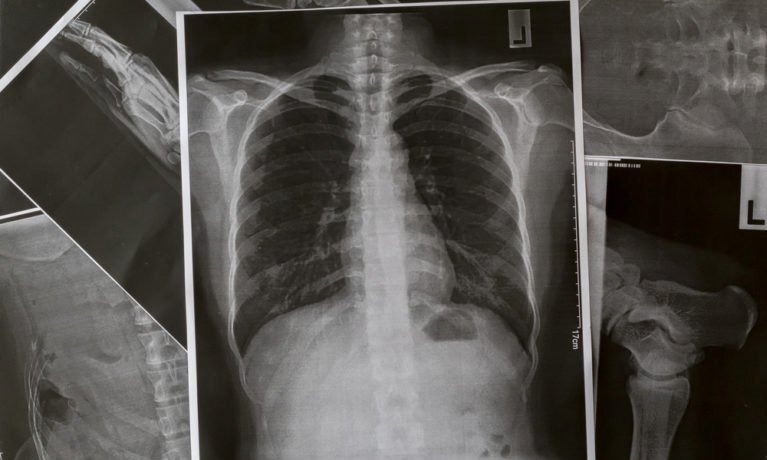

Theo Reader’s Digest, thuyên tắc phổi là một căn bệnh nghiêm trọng xảy ra khi cục máu đông làm tắc nghẽn mạch máu trong phổi. Cục máu đông thường phát triển ở một phần cơ thể (thường là chân) và sau đó theo máu đến phổi.

Ở một số bệnh nhân, dấu hiệu đầu tiên của thuyên tắc phổi là sau khi cục máu đông xâm nhập. Trong phổi. Triệu chứng phổ biến nhất là khó thở. Bệnh thường tiến triển đến mức nguy kịch khá nhanh. Bệnh nhân có thể cảm thấy khỏe vào ban đêm, nhưng khó thở vào sáng hôm sau. Trong một nghiên cứu trên Tạp chí Y học New England, 17% bệnh nhân đã qua đời có cục máu đông trong phổi. Dấu hiệu cảnh báo thuyên tắc phổi. Khi một phần chức năng của phổi bị suy giảm, mất oxy trong tim có thể gây ra cảm giác đau và khó chịu.